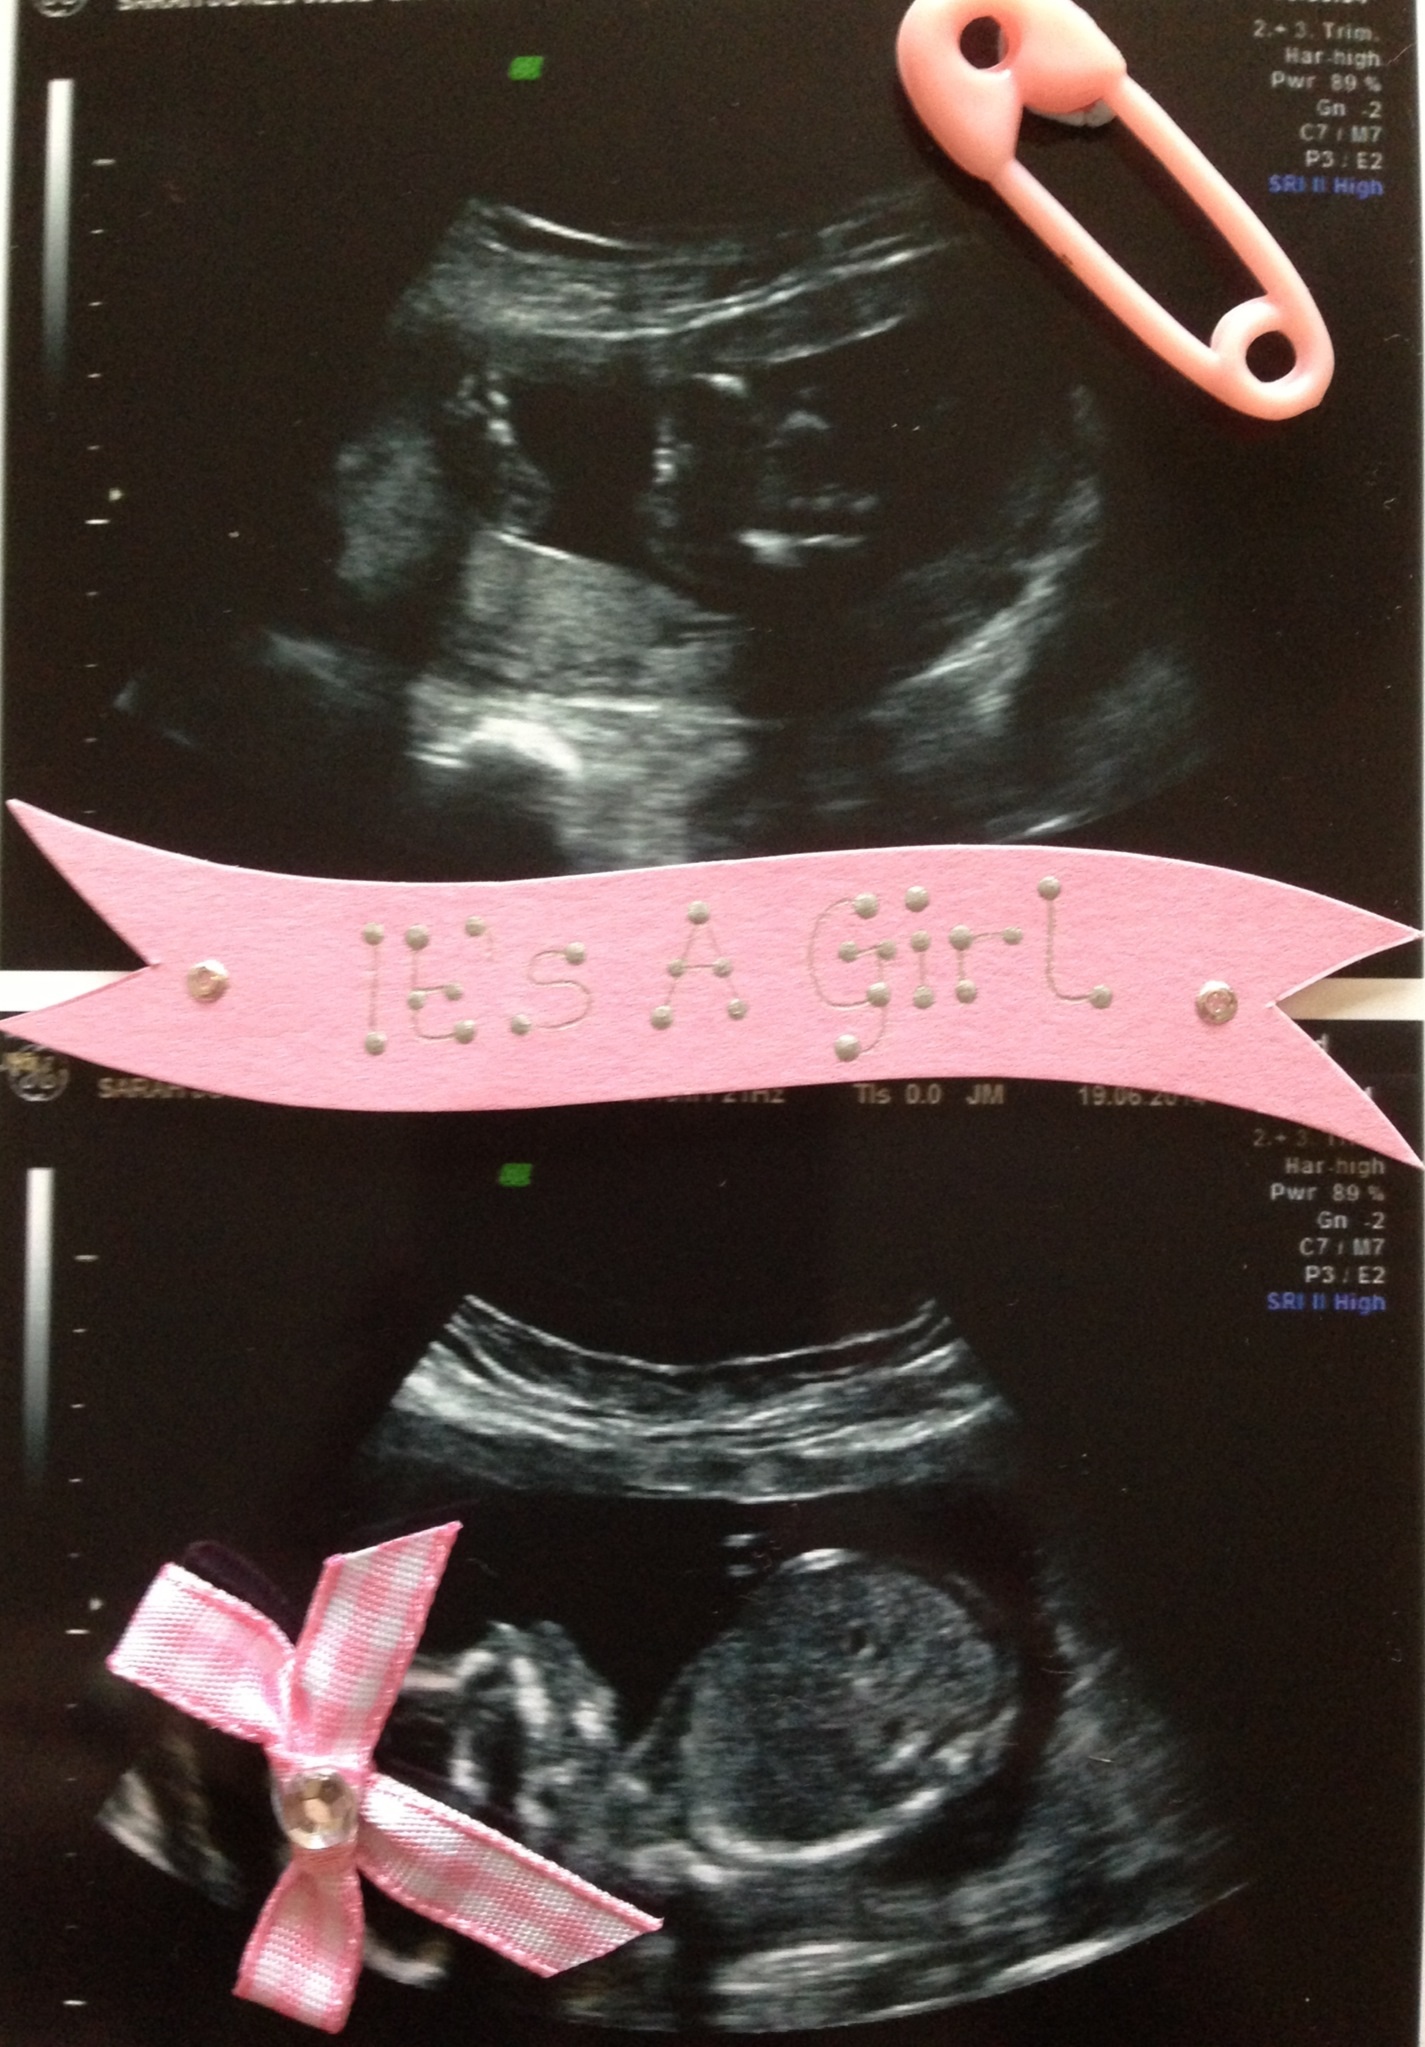

Gender scan on Thursday!! The wait is so difficult I'm praying its....

If that top pic is showing the nub, I'd have to say girl :)

Baby was upside down so I've just flipped it over? Don't know if that would change angle of nub??

Mmmm if the baby was upside down then nub shot doesn't count,hope u hear girl though xx

That is a girl nub if I've ever seen one. However being upside down does make it null and void in theory but I still bet on that being a girl

It's a GIRL!!!! I can't believe it thanks for all of your guesses x